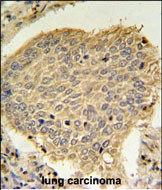

- TPC6A Antibody (N-term) (Cat. #P30665) IHC analysis in formalin fixed and paraffin embedded human lung carcinoma followed by peroxidase conjugation of the secondary antibody and DAB staining. This data demonstrates the use of the TPC6A Antibody (N-term) for immunohistochemistry. Clinical relevance has not been evaluated.